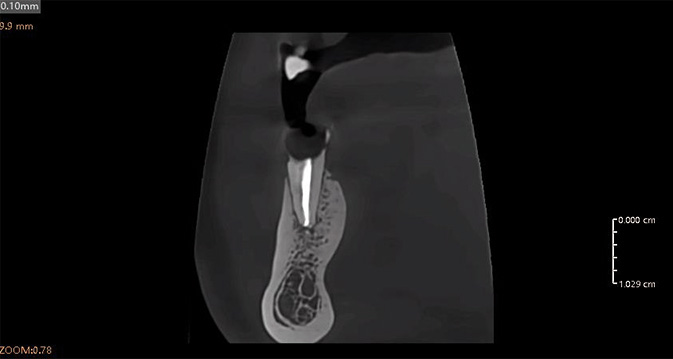

Análisis Endodóntico Impulsado por IA

El módulo de endodoncia de IA detecta y aísla automáticamente cada diente, proporcionando tres modos de visualización 3D: superficie, conducto radicular y transparencia. Esto permite una observación precisa de la morfología, el número y el detalle del conducto radicular, ayudando a los clínicos a realizar diagnósticos y mediciones precisas con facilidad.

Al-Powered: detección rápida y precisa de enfermedades

Precisión impulsada por IA: visualización óptima de las condiciones

Herramientas mejoradas para la comunicación con los pacientes